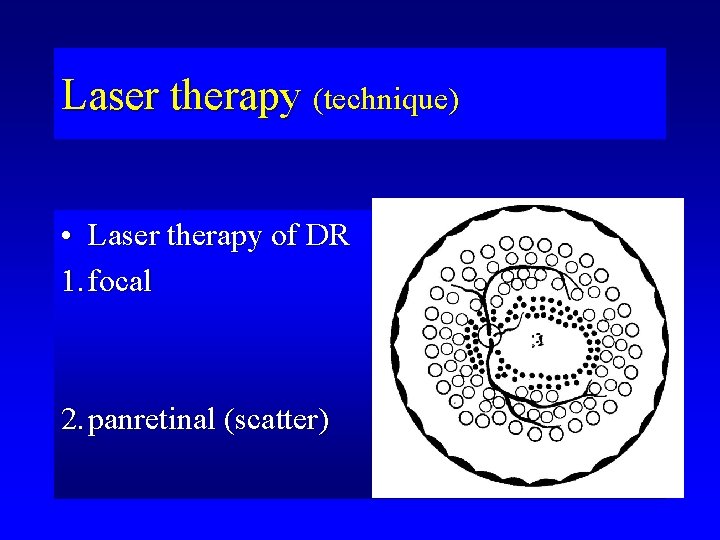

Laser therapy (technique) • Laser therapy of DR 1. focal 2. panretinal (scatter)

Laser spots in retina suffered from NPDR